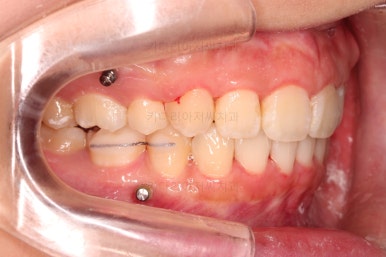

교합, 과개교합 모두 좋아졌고요.

발치 공간도 깔끔하게 닫히고 종료했습니다.

이제 부산무턱교정치과 전후 비교해 볼게요.

옆라인에서도 입술 다물기가 훨씬 편해졌고요.

아래턱에 비해서 나와있던 입술도 뒤로 많이 들어갔고, 턱끝의 방향이 조금 달라지면서 턱이 많이 살아나 보이네요.

전반적으로 만족스러운 치료 결과였습니다.